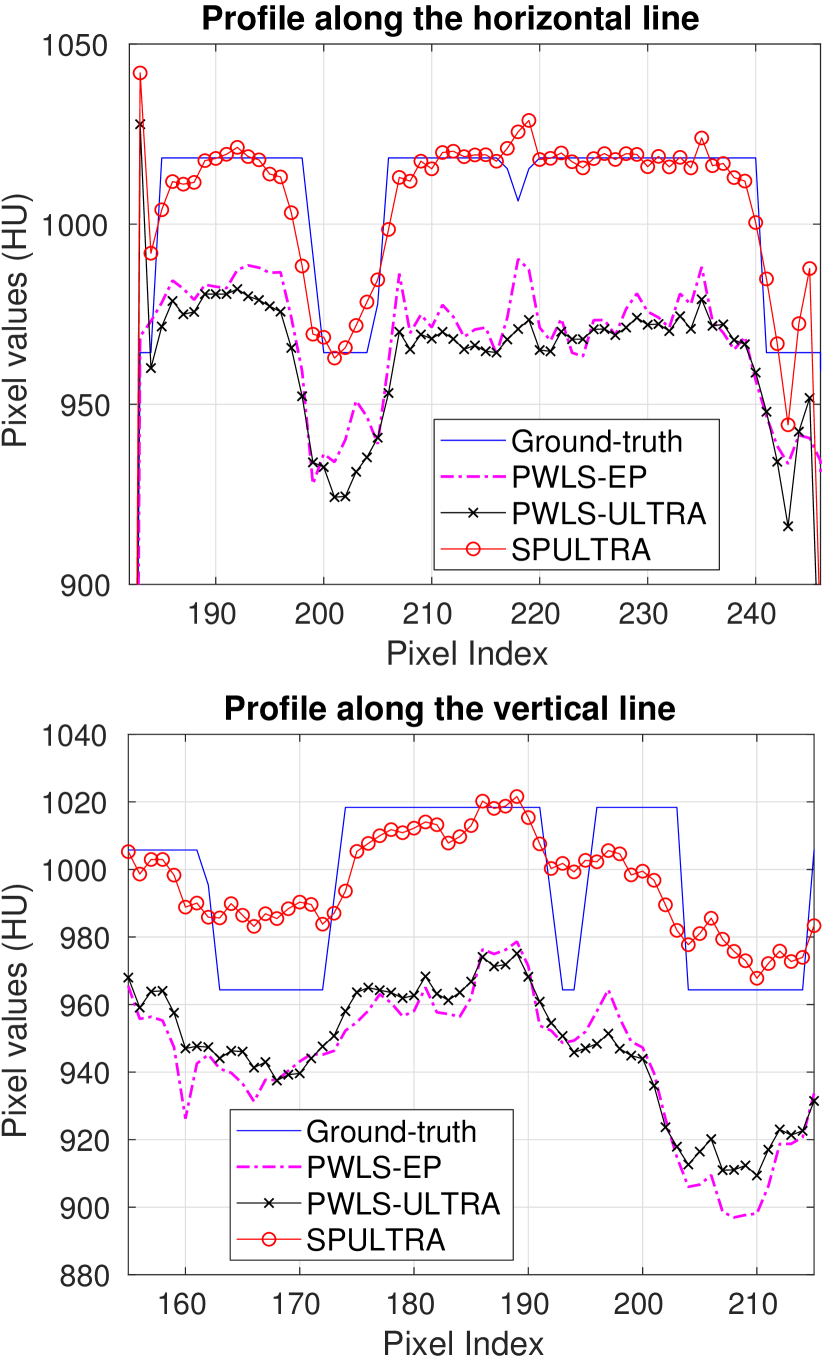

Fig. 4 shows the reconstructed images and the corresponding error images for PWLS-EP, PWLS-ULTRA, and SPULTRA, at and . Compared to the PWLS-EP result, both PWLS-ULTRA and SPULTRA achieved significant improvements in image quality in terms of sharper reconstructions of anatomical structures such as bones and soft tissues, and suppressing the noise. However, the PWLS-ULTRA method introduces bias in the reconstructions, which leads to larger reconstruction errors compared to the proposed SPULTRA method. In Fig. 4, we marked three 3D ROIs in the axial plane, i.e., ROI 1, ROI 2, and ROI 3. Fig. 5 shows the zoom-in images of a 3D plot of ROI 1, and those of ROI 2 and ROI 3 are shown in the supplement. We also plot the evolution of RMSE through the axial slices of the three 3D ROIs in Fig. 6. The figures demonstrate that SPULTRA clearly outperforms the competing PWLS-EP and PWLS-ULTRA schemes.

The above advantages of SPULTRA can be seen more clearly when observing the image profiles. Fig. 7 plots the image profiles for the three methods together with that of the ground-truth image. Fig. 4 shows the horizontal green solid line and the vertical red dashed line, whose intensities are plotted in Fig. 7. It is obvious that the profiles for SPULTRA are closest to the ground-truth among the three compared methods. The gap between the profiles of the PWLS-based methods and the ground-truth shows the bias caused by the compared PWLS methods.